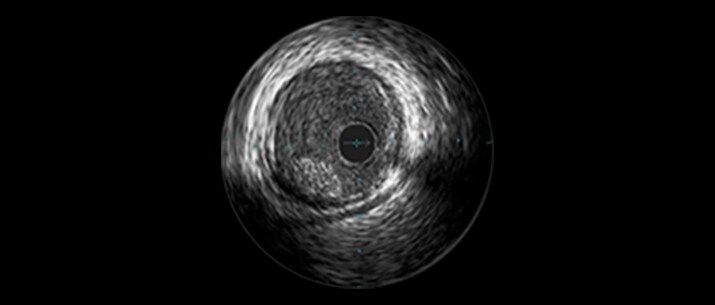

SVG patency rates have been reported at approximately 80% at 1 year and approximately 50% at 15 years and beyond.1